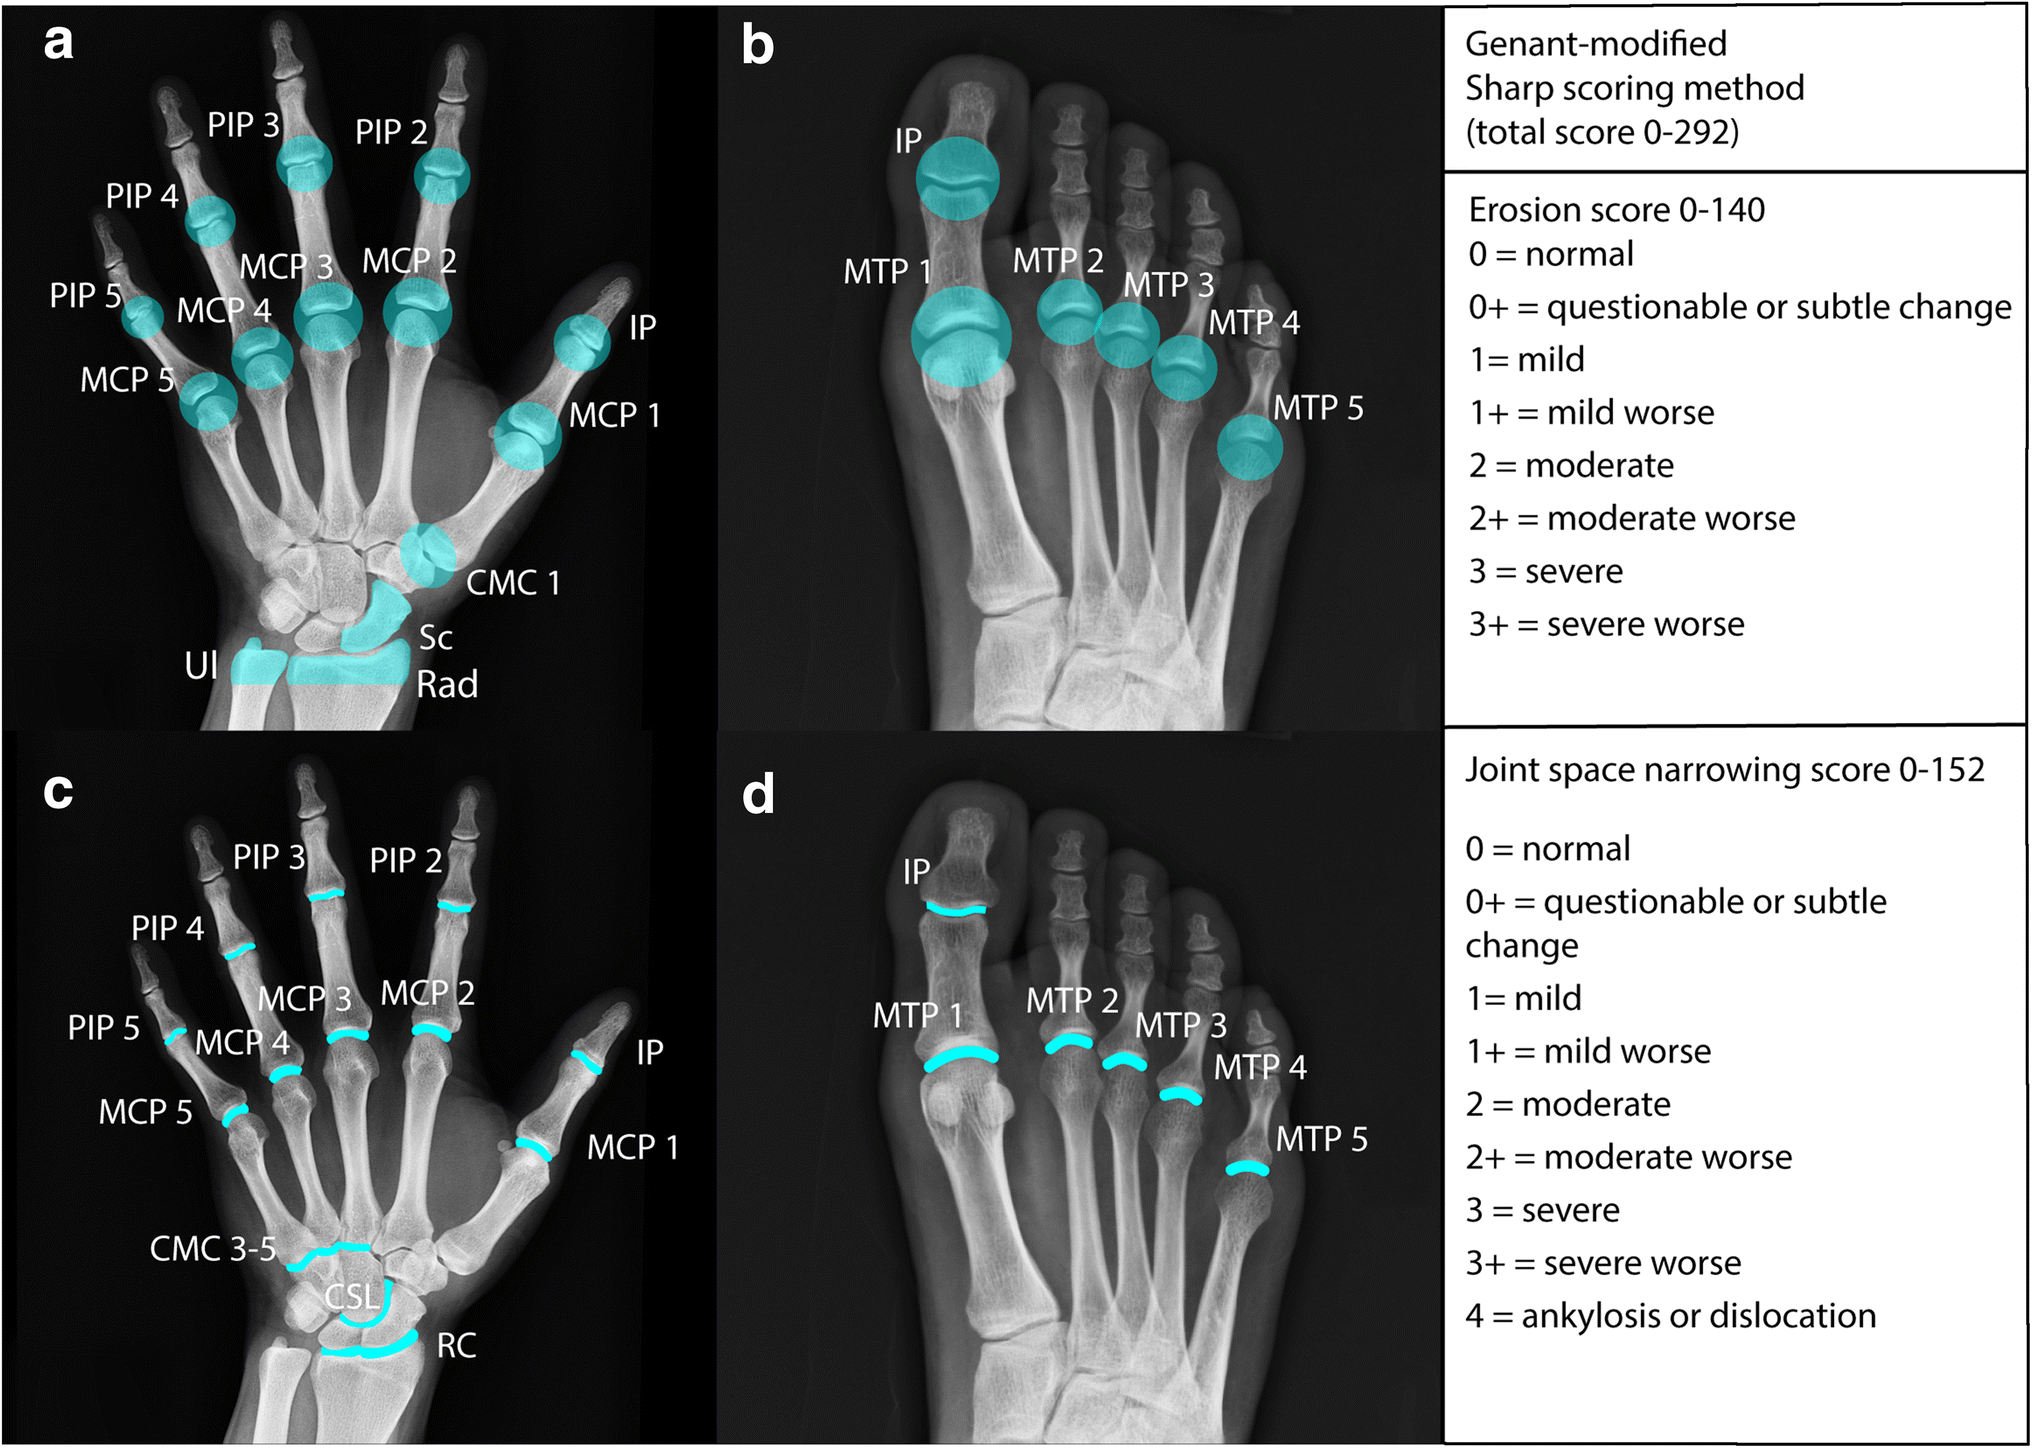

Choose from 500 different sets of flashcards about hand anatomy on quizlet. Use an interactive image to explore the anatomy of the hand and wrist the bones of the hand and wrist provide the body with support and flexibility to manipulate objects in many different ways. The first joint, closest to the knuckle joint, is the proximal interphalangeal joint or pip joint.

Learn about hand anatomy with free interactive flashcards. The hand in the human body is made up of the wrist, palm, and fingers. In this episode of eorthopodtv, orthopaedic surgeon, randale c. They act with the superficialis tendons to flex the wrist and mcp and pip joints.